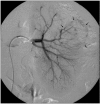

Spontaneous renal hemorrhage (SRH) is a difficult diagnostic problem with various causes. We report a case of SRH and episodic gross hematuria in a patient with metastatic choriocarcinoma involving both kidneys for which successful angioembolization was carried out for control of hemorrhage. There was no evidence of primary uterine tumor and pulmonary or liver involvement. The patient developed gastrointestinal bleeding due to jejunal metastasis while on chemotherapy and surgical resection of the involved segment was carried. However, the patient acquired nosocomial pneumonia and succumbed to sepsis in the postoperative period.